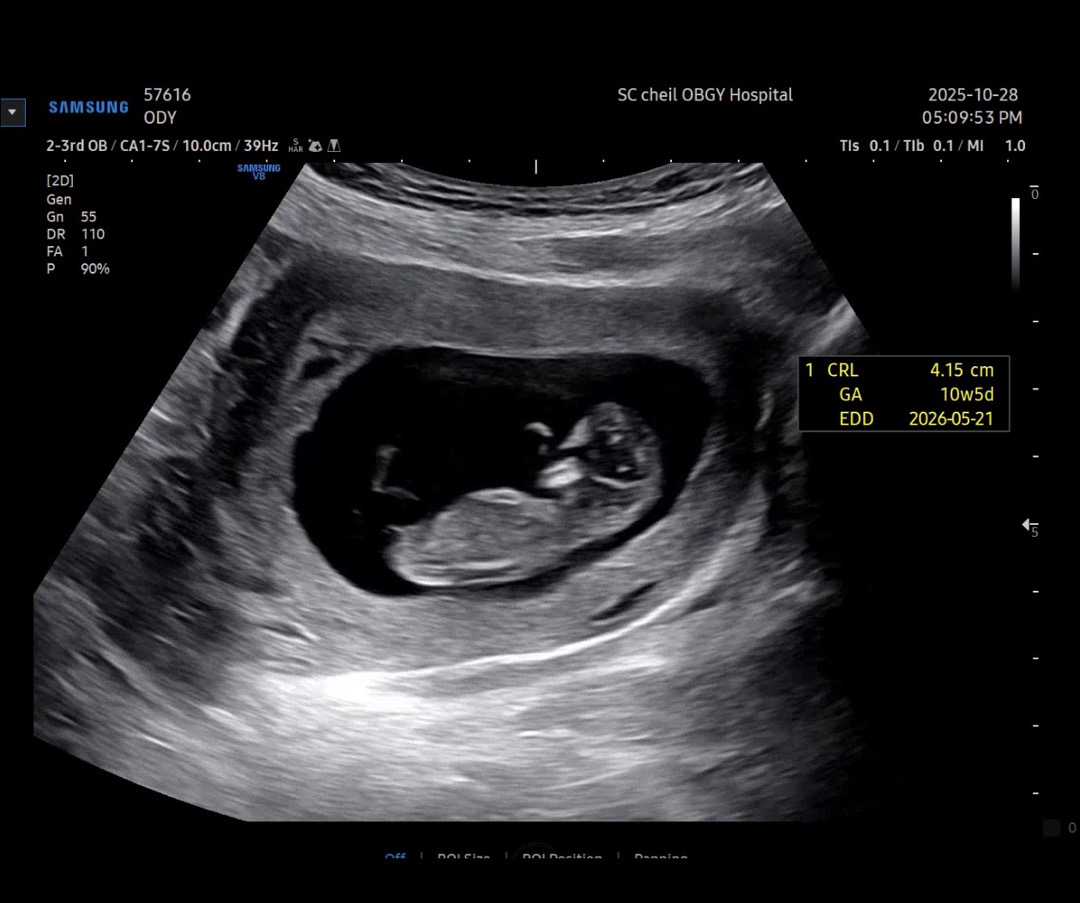

10주5일차 성별 궁금 ㅎ

각도법 고수이신분들 알려주세요 ㅎㅎㅎㅎㅎ